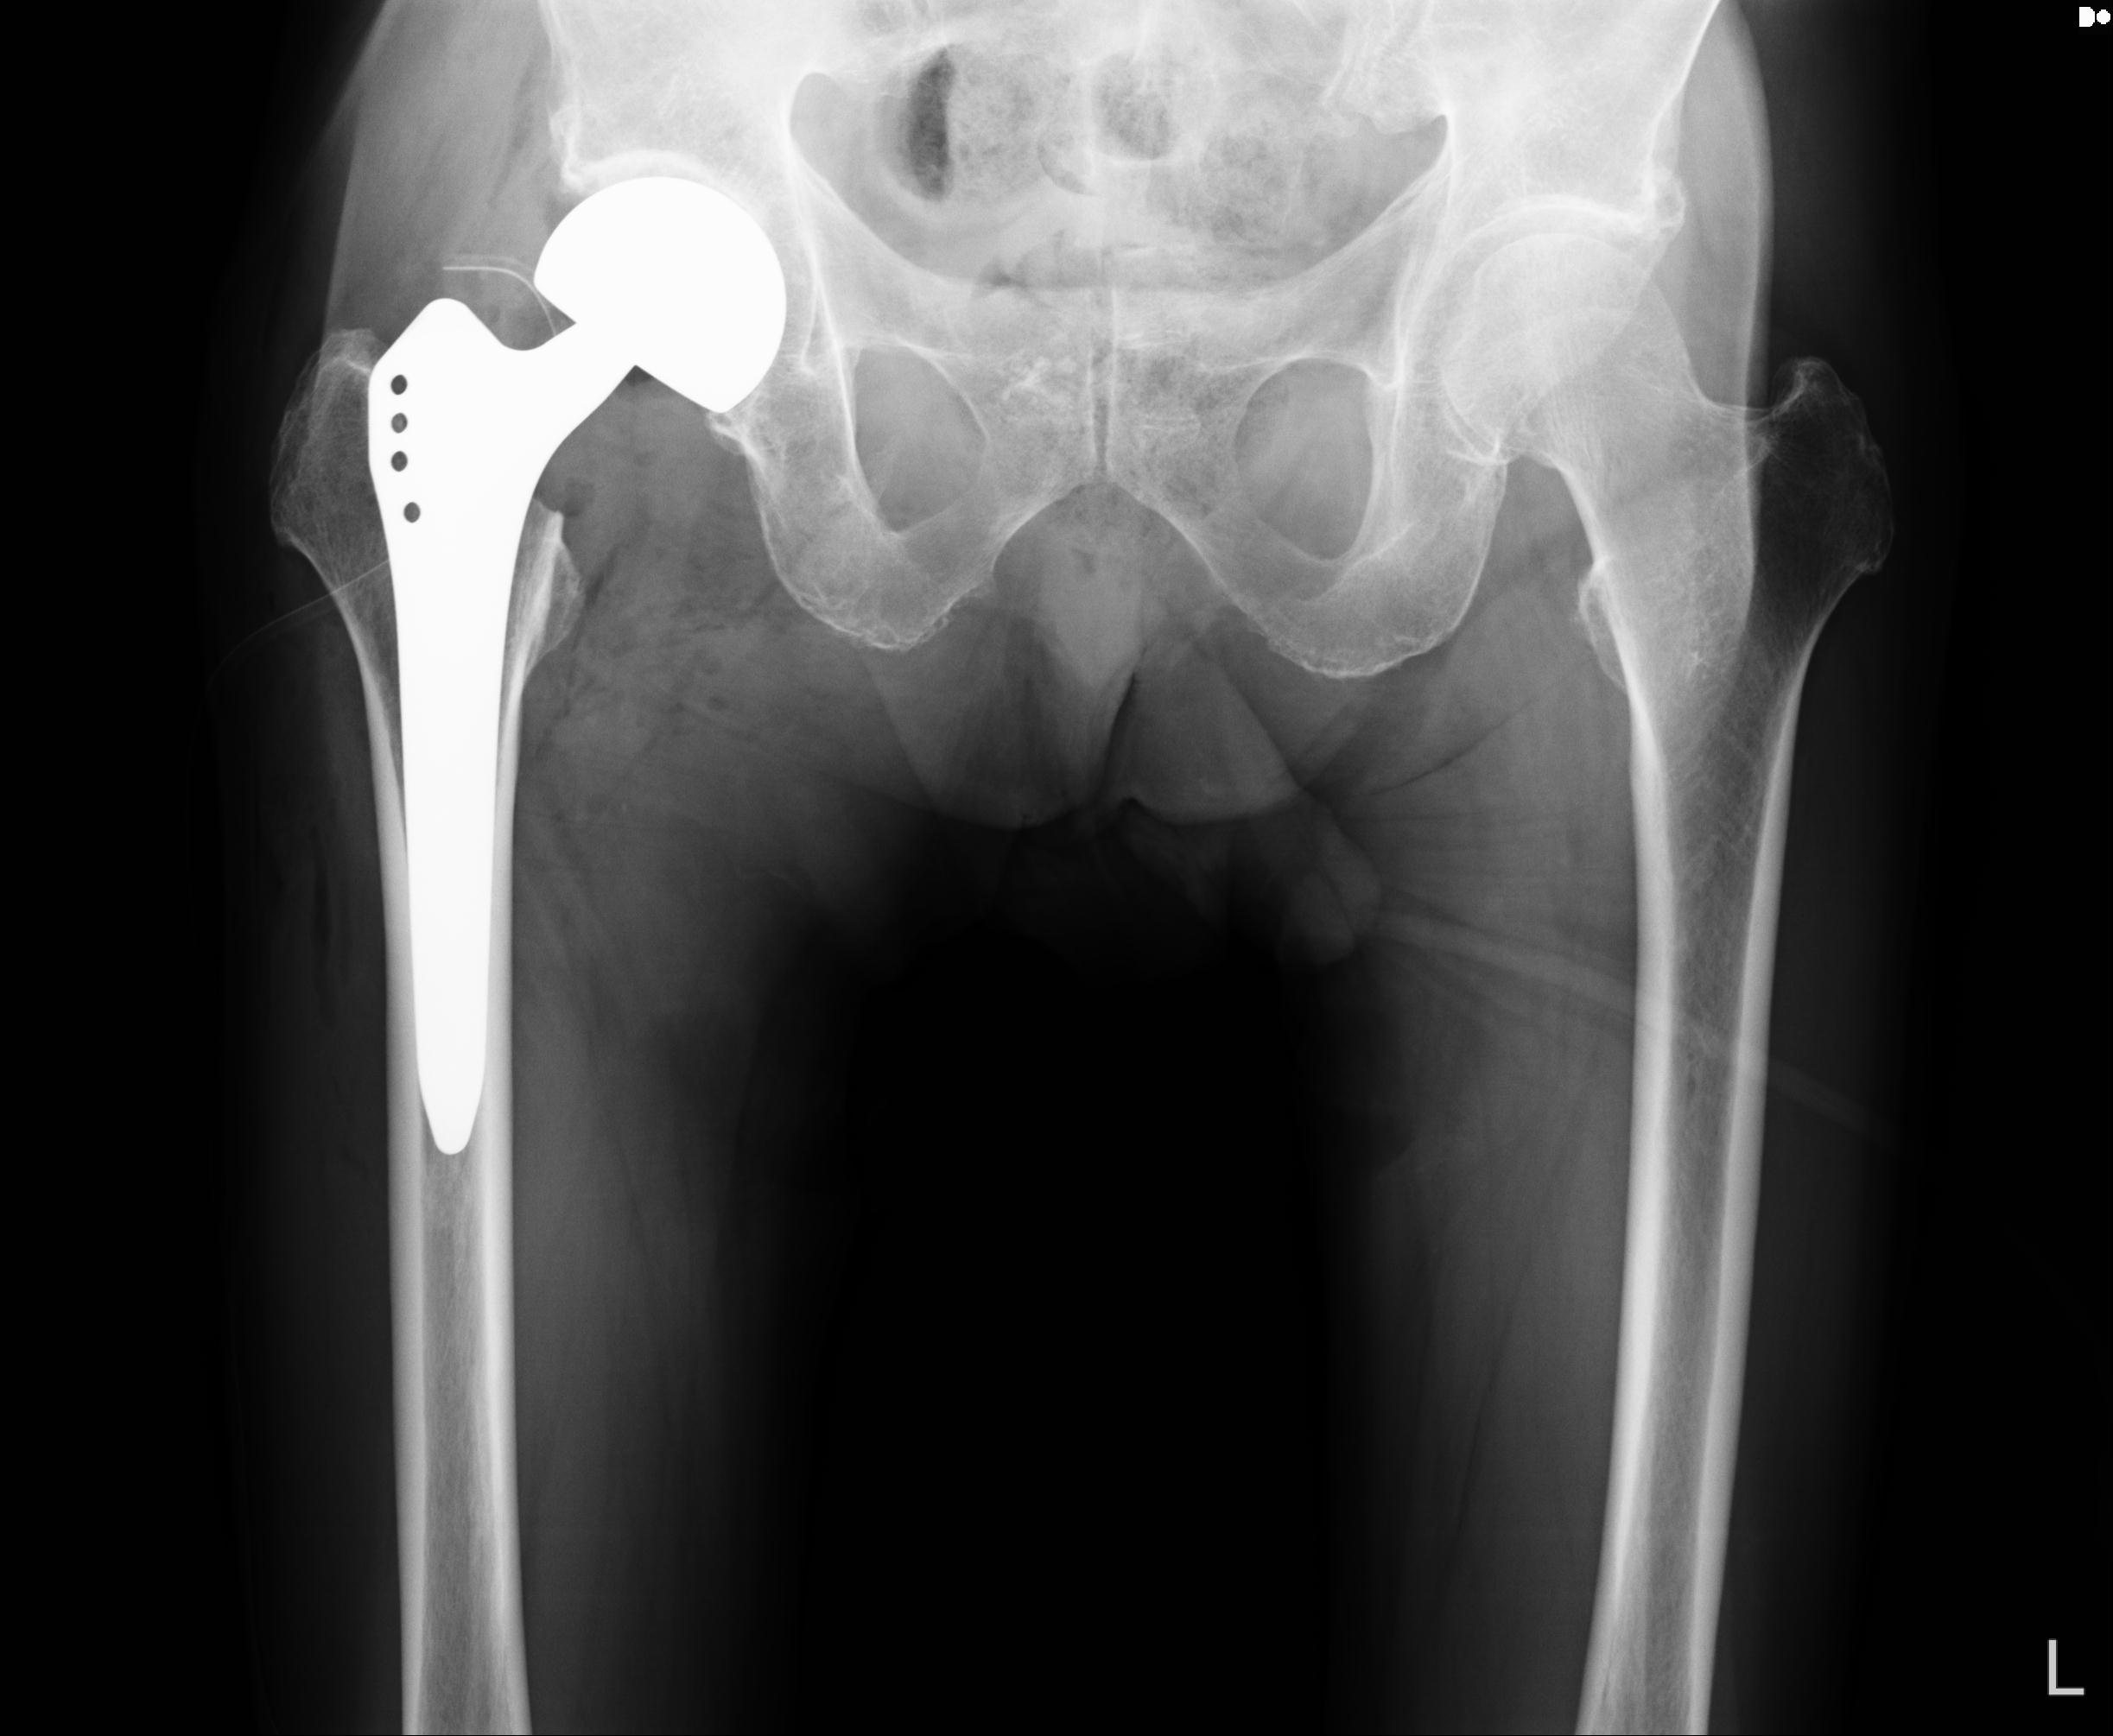

110286 2/17 股関節 2R 74歳女性 右人工骨頭

82084 1/14 1/20 股関節 2R 78歳男性 右人工骨頭

102811 1/13 股関節 2R 1/19 2R 80歳女性 右DHS

91569 3/25 両股正面とラウエン 70歳女性 人工骨頭+バンクーバー